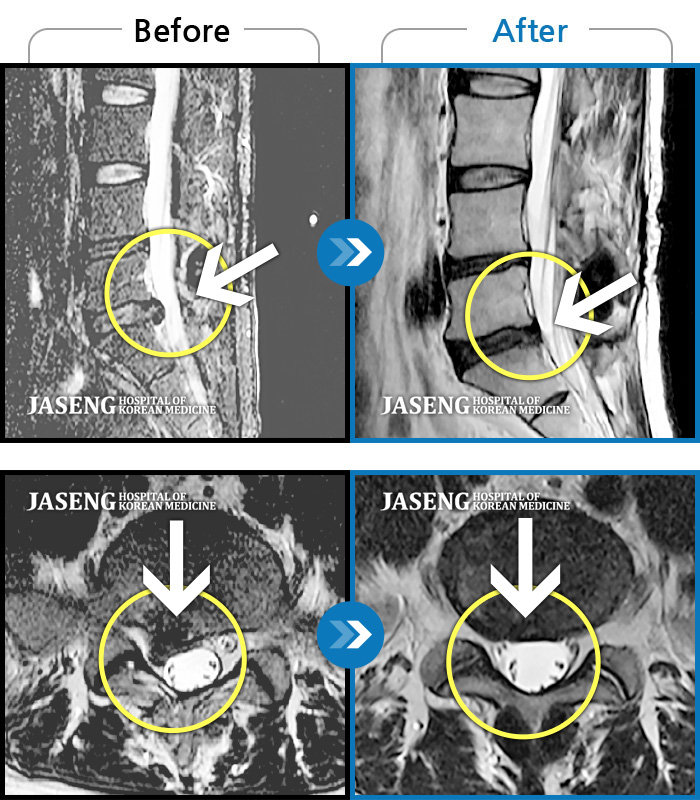

ȯںп Ǹ ǿ ԿǾ, ο ġ ۿ Ƿ ġḦ Ͻñ ٶϴ.